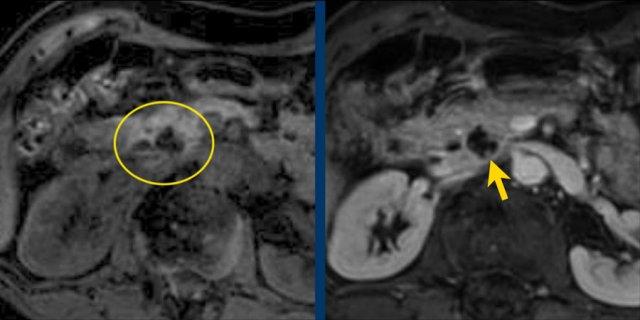

Trên chuỗi xung T2W, tổn thương có dạng đa nang.

Lưu ý vùng giảm tín hiệu trung tâm do sẹo trung tâm kèm vôi hóa.

Mặc dù một số nang có kích thước khá lớn, đây vẫn là hình ảnh đặc trưng của u nang tuyến thanh dịch (dạng đại nang).

Một ví dụ khác về u nang tuyến thanh dịch (Hình).

Hình ảnh sau tiêm thuốc cản quang bên phải cho thấy tổn thương giảm tỷ trọng với vôi hóa trung tâm ở thân tụy và ngấm thuốc nhẹ của các vách ngăn.

Lưu ý rằng trên CT rất khó nhận ra bản chất dạng nang của các tổn thương này và có thể nhầm lẫn với ung thư biểu mô tuyến tụy.

MRI sẽ dễ dàng thể hiện bản chất dạng nang của các tổn thương này (hình).

Chuỗi xung T2W với xóa mỡ (fatsat) thể hiện rõ tổn thương tăng tín hiệu dạng thùy múi với sẹo trung tâm, đây là hình ảnh đặc trưng của SCN.